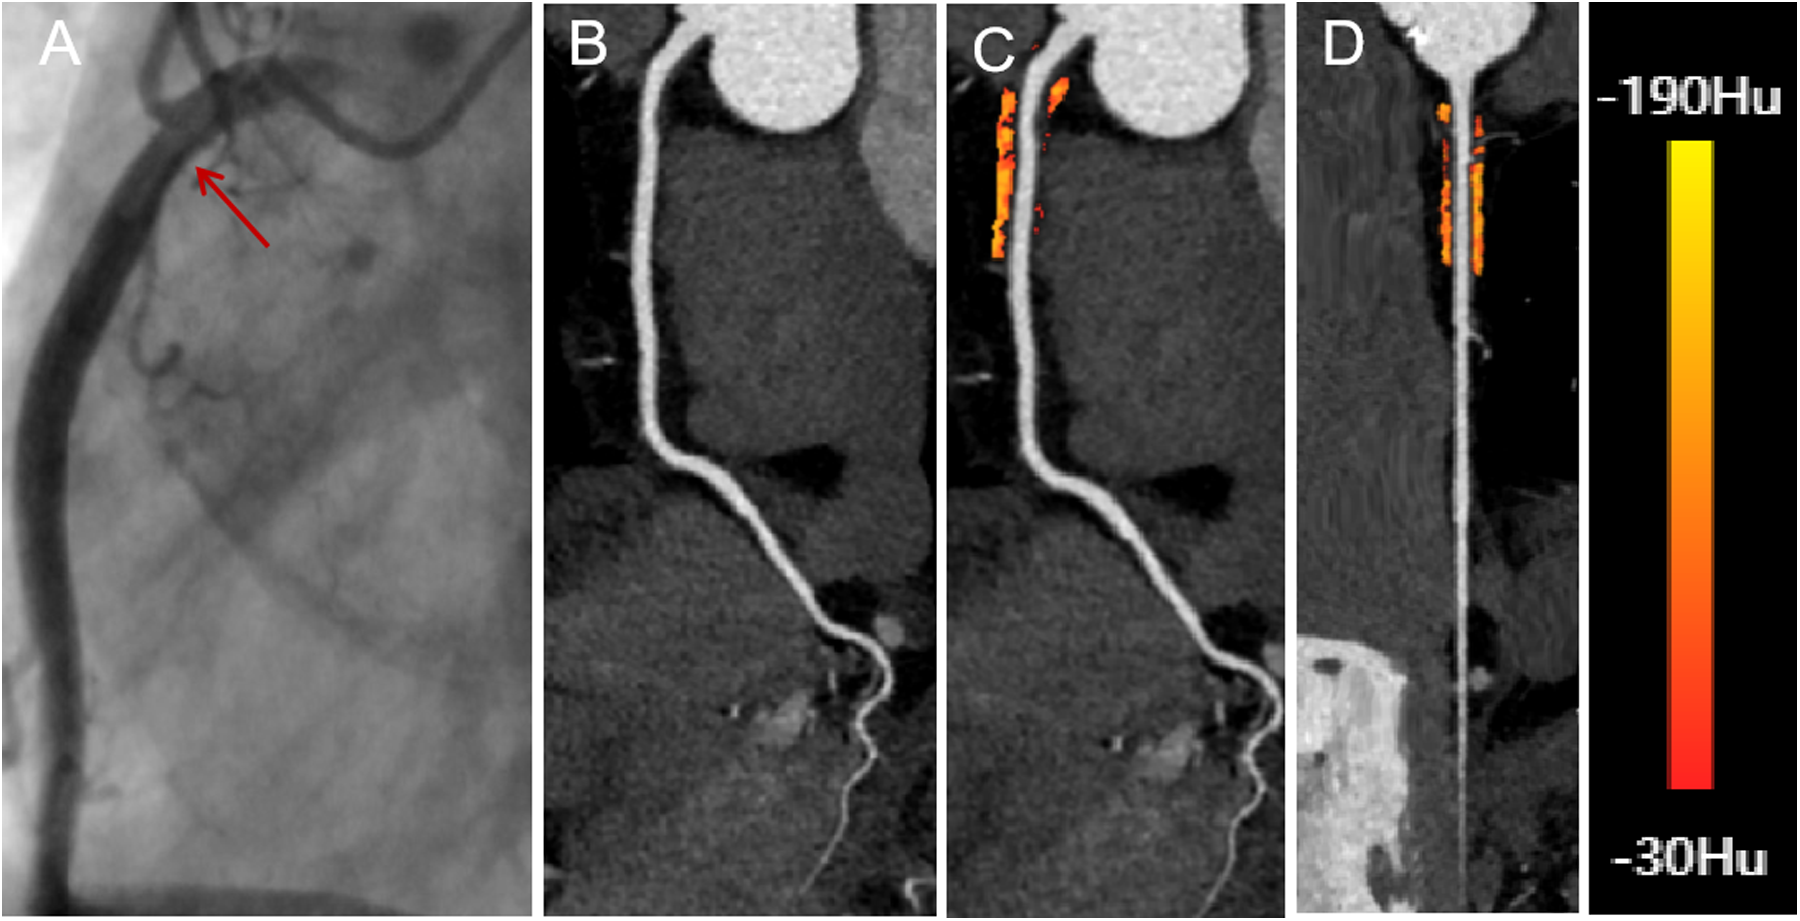

Figure 2

A 66-year-old male with insignificant hemodynamic stenosis in the proximal segment of the right coronary artery. (A) The red arrow shows a narrowing of 30% in the DSA. (B) CCTA with curved planar reformation of the right coronary artery shows non-calcified plaque formation in the proximal segment, with an approximate lumen narrowing of 15%. (C) A representative curved planar reformation image reveals a FAI [−81 HU] of PCAT, suggesting non-ischemic coronary artery narrowing. (D) FAI color maps of the PCAT in the proximal 10–50 mm of the right coronary artery, with a probe straightening image. PCAT color map ranges from red [−30 HU] to yellow [−190 HU]. CCTA, coronary computed tomography angiography; DSA, digital subtraction angiography; FAI, fat attenuation index; PCAT, pericoronary adipose tissue.

The PCAT volume and FAI were calculated for the proximal 10–50 mm of the RCA and the proximal 0–40 mm of the LAD and LCX arteries. For the RCA, the first 10 mm of PCAT was excluded to minimize partial volume effects and artifacts caused by intraluminal contrast (25). In cases where the RCA length was less than 50 mm, the proximal limit of PCAT measurement was adjusted to within 0–10 mm of the RCA orifice. Coronary branches of the RCA and adjacent myocardial tissue were excluded from the automated PCAT analysis to avoid confounding factors (24).